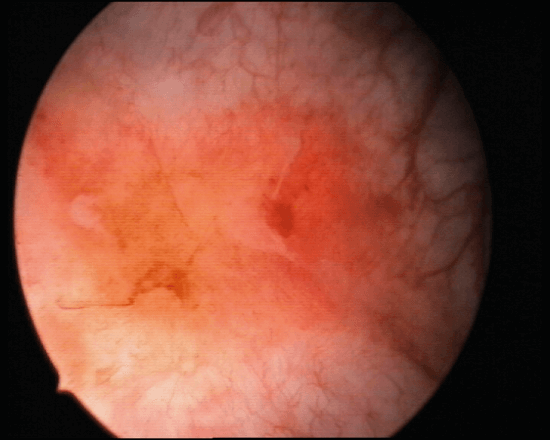

Figure 1: Hunner’s ulcer.

Figure 2: post distension glomerulations. Interstitial cystitis / bladder pain syndrome (BPS).

BPS is classified on cystoscopic appearances by the ESSIC into normal (grade 0), glomerulations grade II-III (grade I denoted petechiae in at least two quadrants), and Hunner’s lesions. Cystoscopy findings combined with histological on biopsy enables a more detailed classification as per the ESSIC guidelines.